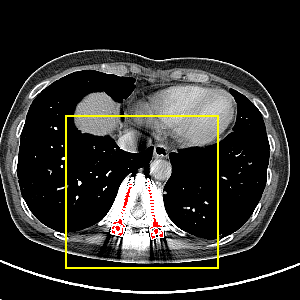

Visual comparison. As shown in Fig. 5, metallic implants such as spinal rods and hip prosthesis cause severe streaky artifacts and metal shadows, which obscure bone structures around them. cGan-CT cannot recover image intensity correctly for both cases. Sinogram domain or dual-domain methods perform much better than cGan-CT. LI, NMAR, and CNNMAR introduce strong secondary artifacts and distort the whole images. In NMAR images, there are fake bone structures around the metals, which is related to segmentation error in the prior image from strong metal artifacts. The segmentation error is also visible in NMAR sinogram. CNNMAR cannot restore the correct bone structures between rods in case 1. The tissues around the metals are over-smoothed in DuDoNet because LI sinogram and image are used as inputs, and the missing information cannot be inferred later. Our model retains more structural information than DuDoNet and generates anatomically more faithful artifact-reduced images.

Visual comparison. Fig. 7 shows two clinical CT images with metal artifacts. Case 1 is with moderate metal artifacts. cGan-CT does not suppress the artifacts completely and generates some fake details. LI, NMAR, CNN-MAR remove all the artifacts but introduce new streak artifacts, which is caused by the discontinuity in the corrected sinogram. DuDoNet outputs over-smoothed sinogram, which leads to blurred tissues close to the metal implants, such as muscle and bone. Only our model can provide realistic enhanced sinogram and remove the artifacts while retaining the structure of nearby tissues. Case 2 is very challenging as the rods bring strong metal shadows and bright artifacts around the vertebra. cGan-CT recovers the shape of vertebra but changes the overall image intensity. Other sinogram inpainting methods fail as the soft tissue and bone near the rods are heavily distorted. Our model removes part of the dark bands and reproduces correct anatomical structures around the rods.